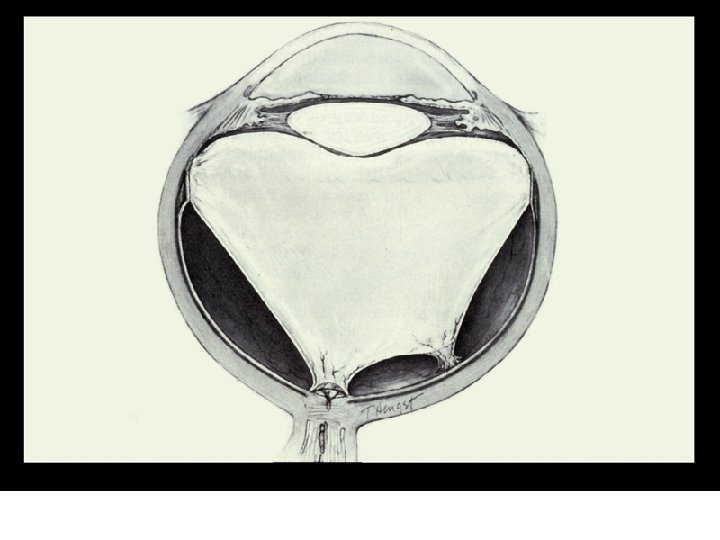

Persistent Hyperplastic Primary Vitreous

III. DEVELOPMENT OF THE VITREOUS z. A. The primary vitreous develops at the end of the third embryonic week y 1. the primary vitreous is behind the lens vesicle and is formed by mesoderm that migrates between the optic cup and the lens vesicle y 2. is primarily the hyaloid vasculature xa. artery that supplies nutrients to the tissue behind the lens and the lens

III. DEVELOPMENT OF THE VITREOUS xb. the hyaloid vasculature dissolves before birth • i. the process is autolytic, i. e. the vasculature dissolves itself • ii. no macrophages enter the area from outside xc. the canal that is left after the primary vitreous dissolves is called the canal of Cloquet or the hyaloid canal xd. floaters

III. DEVELOPMENT OF THE VITREOUS y 4. eventually fills the globe and compacts the primary vitreous xa. there is a condensed area of vitreous that separates the primary and secondary vitreous y 5. the secondary vitreous has a condensed area of vitreous at its periphery xa. acts like an outer skin

III. DEVELOPMENT OF THE VITREOUS z. C. The tertiary vitreous (zonular fibers) begins to develop at 6 months embryonically y 1. the fibrous structure of the secondary vitreous condenses and forms the zonules y 2. the zonules merge with the lens capsule and the basement membrane of the ciliary body